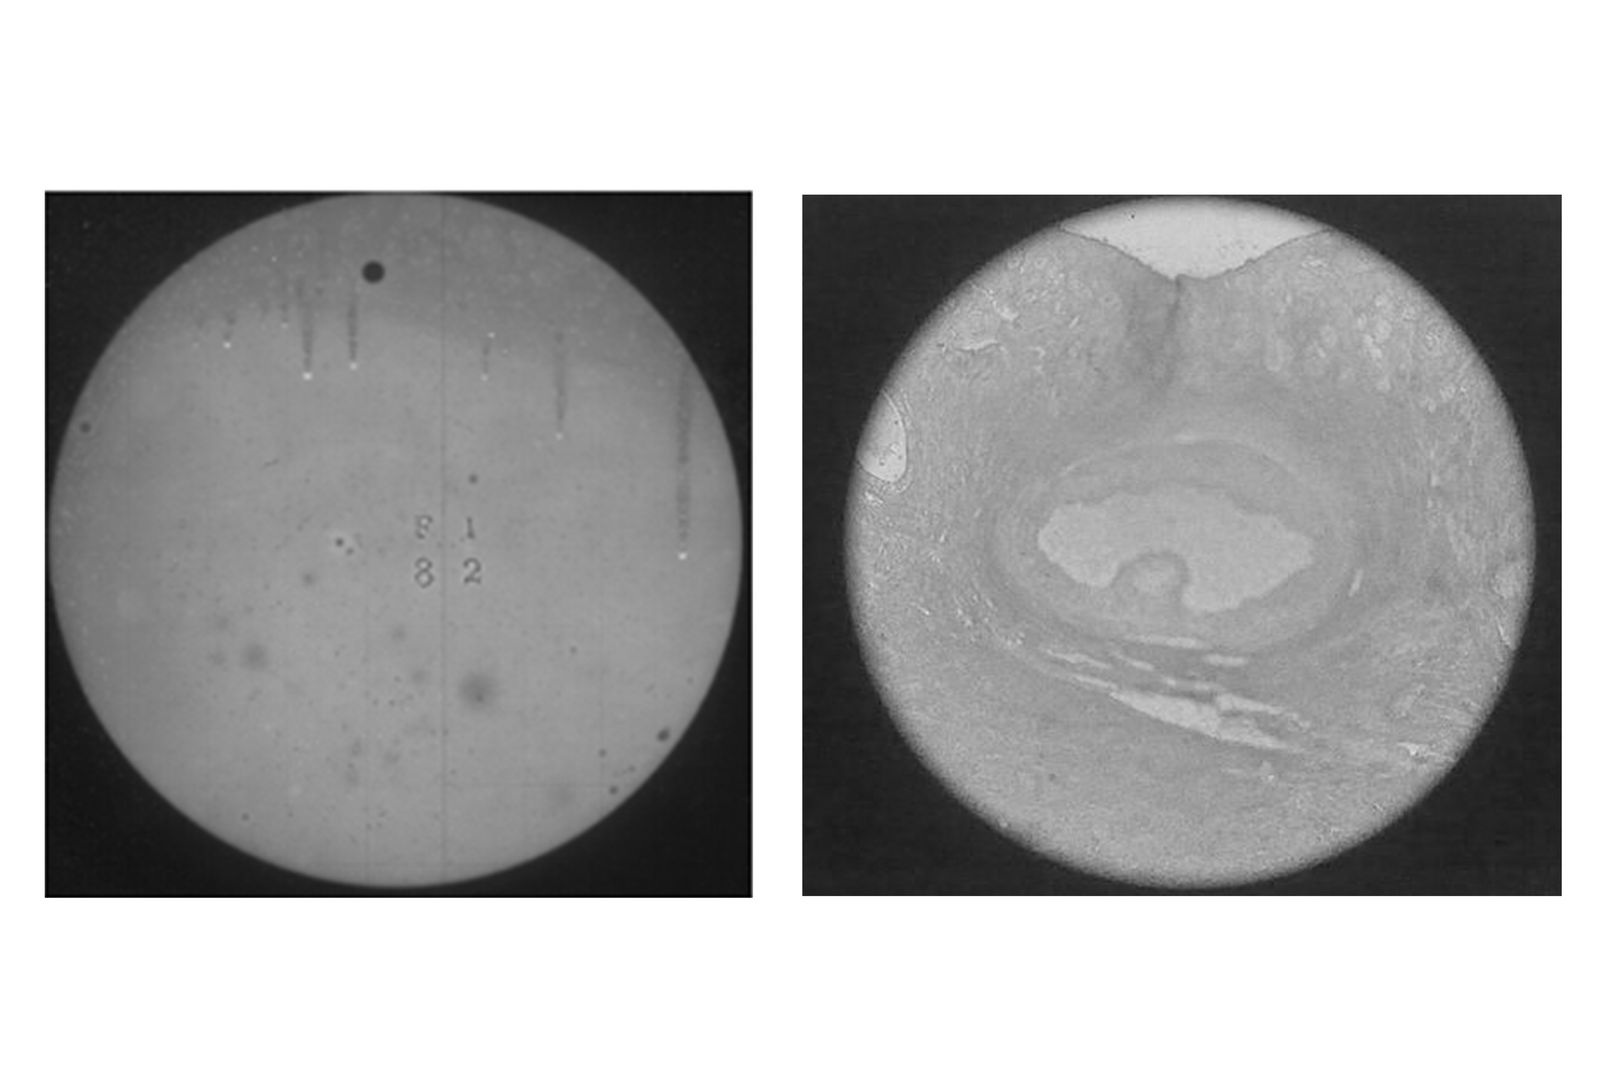

© Xanthe Hutchinson - L: The Transit of Venus R: Histology of an Ovary

L: The Transit of Venus R: Histology of an Ovary